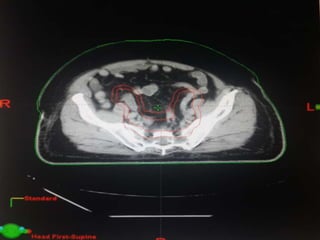

RTOG GU Consensus on pelvic LN CTV volumes:

 Commence contouring the pelvic CTV LN volumes at the L5/ S1

interspace (the level of the distal common iliac and proximal

presacral lymph nodes).

 Place a 7-mm margin around the iliac vessels connecting the

external and internal iliac contours on each slice, carving out

bowel, bladder, and bone.

 Contour presacral lymph nodes from S1 through S3, posterior

border being the anterior sacrum, and anterior border

approximately 10 mm anterior to the anterior sacral bone

carving out bowel, bladder, and bone.

 Stop external iliac CTV lymph node contours at the top of the

femoral heads (bony landmark for the inguinal ligament).

 Stop contours of the obturator CTV lymph nodes at the top of

the symphysis pubis.

Our unit decide to treat:

 Prostate + S.V & prophylactic Pelvic LNs in

phase1

 Prostate + S.V phase 2

 Delineation of our unit illustrated in the

following slides:

RTOG GU Consensuson pelvic LN CTV volumes:  Commence contouring the pelvic CTV LN volumes at the L5/ S1 interspace (the level of the distal common iliac and proximal presacral lymph nodes).  Place a 7-mm margin around the iliac vessels connecting the external and internal iliac contours on each slice, carving out bowel, bladder, and bone.  Contour presacral lymph nodes from S1 through S3, posterior border being the anterior sacrum, and anterior border approximately 10 mm anterior to the anterior sacral bone carving out bowel, bladder, and bone.  Stop external iliac CTV lymph node contours at the top of the femoral heads (bony landmark for the inguinal ligament).  Stop contours of the obturator CTV lymph nodes at the top of the symphysis pubis.

Our unit decideto treat:  Prostate + S.V & prophylactic Pelvic LNs in phase1  Prostate + S.V phase 2  Delineation of our unit illustrated in the following slides: